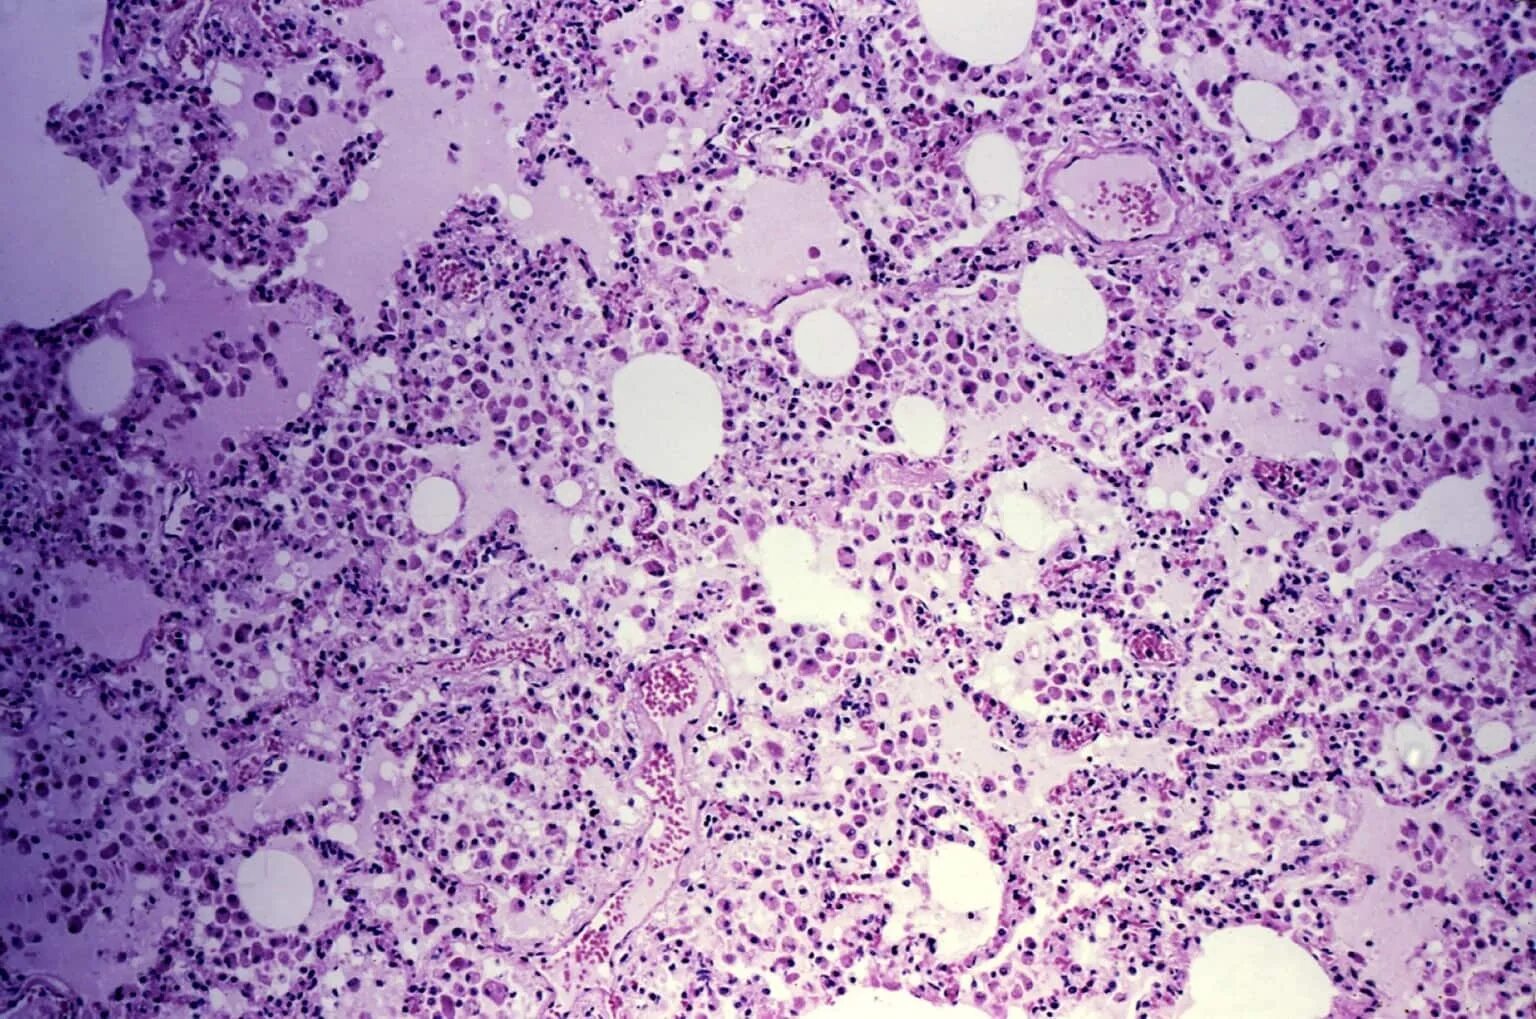

Гистологическая вырезка